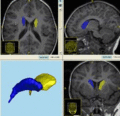

Cause07Competition.gif (262 × 253 pixels, file size: 41 KB, MIME type: image/gif)

| current | 20:16, 2 January 2008 | 262 × 253 (41 KB) | Styner (talk | contribs) |